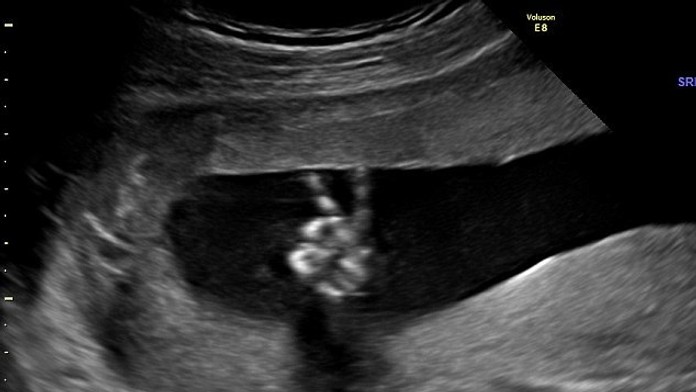

Ultrazvukové vyšetrenie počasa tehotenstva je pre mnohých rodičov veľká vec. To museli absolvovať aj Parsonovci z Godalmingu. Počas neho sa však na obrazovke zjavila neopakovateľnú úkaz. Ich malý 20-týždňový potomok im ukazoval víťazné "V".

"Nemohla som tomu uveriť, ešte nikdy som nič také nevidela," spomína na udalosť budúca matka Parsonová. Je pre ňu vraj veľmi príjemné mať v bruchu takýto ikonický obraz mieru, keď je okolo nej samá vlna nepokojov.

"Prednedávnom nám zomrel niekto veľmi blízky. Mysleli sme si, že naše dieťa príde do sveta negatívnych udalostí, preto si o to viac vážime toto pokojné gesto," tvrdia budúci rodičia.

Už teraz vedia, že v prípade, že to bude chlapec ho nazvú po Winstonovi Churchilovi. Aj práve s ním sa toto V-čkové gesto spája. Preto už teraz, keď sa k bábätku prihovárajú, volajú ho Winston.

Winston Churchill týmto V-čkovým znakom naznačil „víťazstvo" počas vojny. Neskôr sa však toto gesto vo väčšine krajín zmenilo na znak mieru a inak to nie je ani dnes. Existuje však zopár výnimiek, medzi nimi Austrália a Nový Zéland, kde by ste týmto gestom prejavili ľuďom neúctu a nedostatok rešpektu.